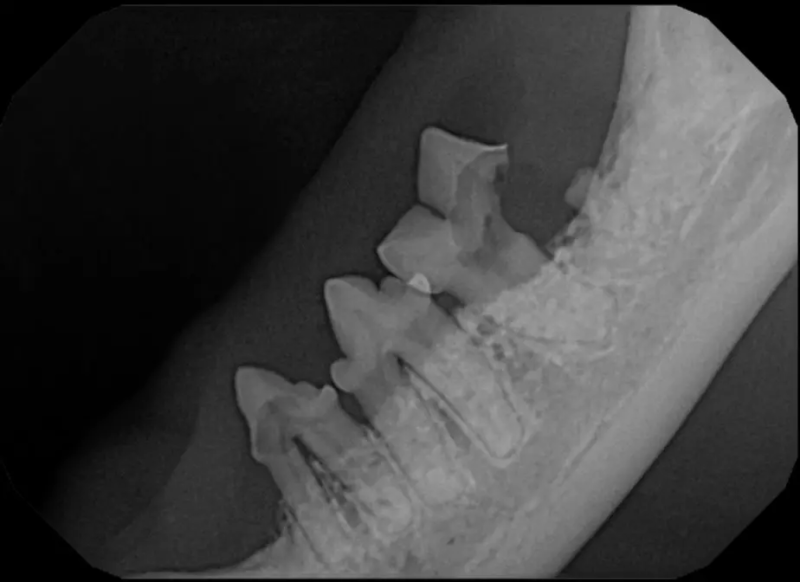

The Center now provides advanced imaging via cone beam CT. Cone beam CT is excellent for visualization of bony structures of the skull, nasal cavity, teeth, and ears. Cone beam CT is especially helpful for diagnosing dental disease and evaluation of jaw fractures. It can also be useful for evaluating the sinuses and tympanic bulla. Cone beam CT can be used in conjunction with nasal biopsy and culture to evaluate nasal discharge whether chronic or acute.

Periodontal disease is extremely common in dogs and cats. Over 80% of dogs and cats over two years of age have some degree of periodontal disease. Periodontal disease is best prevented by yearly professional dental cleanings starting at two years of age and at home brushing at least three times weekly. Brushing should begin at a very early age to allow your new pet to get used to regular brushing. In severe cases of infection or periodontal disease, the teeth may need to be surgically extracted. Extractions should always involve x-rays of the tooth first, as many teeth have multiple roots or may be diseased below where the eye can see. Extracting larger teeth in animals requires oral surgery, equivalent to removing wisdom teeth in people. It is vital that all of the tooth and roots be removed for the periodontal infection to resolve. In cases of important teeth with mild to moderate periodontal disease, multiple periodontal treatments can be offered to help save these teeth.

Pets can be involved in trauma that can cause fractures to their head, teeth, and jaw bones. Correctly repairing these fractures is extremely important for your pet to have normal function of their mouth. If a jaw fracture is allowed to heal in an abnormal position, your pet may have great difficulty chewing and can be in significant pain. Many fractures can be successfully treated with minimally invasive oral procedures, but more complicated cases may require bone plating techniques. The Center offers cone beam CT imaging which provides extremely detailed images of the bones of the head and skull. Advanced imaging with CBCT facilitates selection of the best surgical technique to get your pet back to eating and comfort as soon as possible.